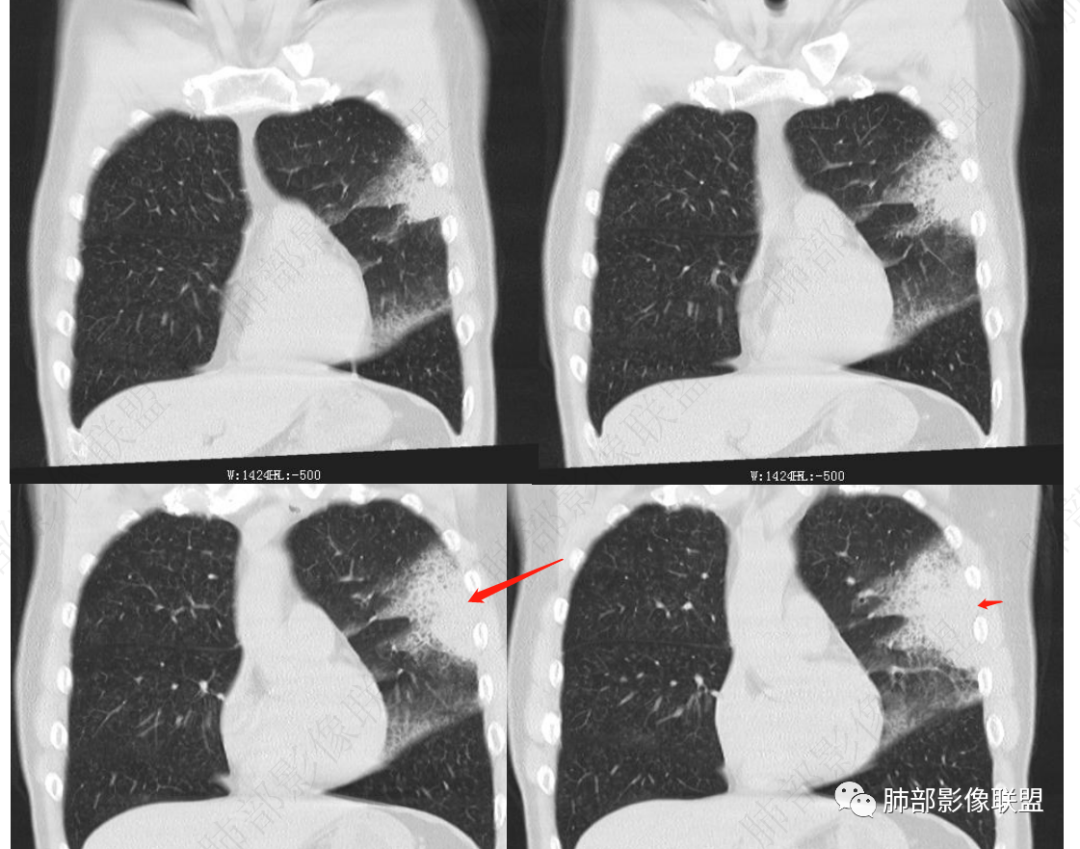

左肺上叶片状实变,内可见多发空泡及蜂窝影,斜裂上方可见相同病灶由于斜裂阻挡呈重力分布,强化可见血管造影征,双肺弥漫分布气腔结节,临床咳白色粘液痰,考虑粘液腺癌

男,46,咳嗽半年,加重10天,白粘痰,偶有痰血。胸部CT:左肺上叶舌叶大片实变影,边缘GGO,长轴沿胸膜及叶裂展开,重力依赖,胸膜叶裂阻隔,内见蜂窝,钱币征,枯枝。强化不均匀,血管造影征。考虑粘液腺癌,鉴别大叶性肺炎、干酪性肺炎等。

46岁男性,病史半年,近期咯血,无肺气肿背景

大片实变灶累及多个段

实变区位于胸膜下,长轴与胸膜平行

实变区内有低密度带,强化偏低,欠均匀

支气管近端通畅,实变区远端堵塞,腔内有粘液栓

血管走形尚自然,没重建血管,没有明显血管受侵

糊墙征   蜂窝征

GGO部分边界清,近实变区密度高

部分肺动脉局部狭窄,考虑局部推压

2.左肺上叶大片状混合密度影,未见空洞,实变影主要位于胸膜下,长轴与胸膜平行,实变区内部密度不均、其内可见多发小斑片状低密度影,磨玻璃影多位居肺门一侧,可见网格,磨玻璃影边界多可分辨,重力分布趋势。病灶区支气管显示较为通畅,进入外围实变区渐至消隐。病灶轻度不均匀低强化,病灶区肺动脉显示较良好,未见破坏。

双肺广泛分布微小磨玻璃密度结节影,腺泡结节样分布,密度大小较为均匀一致。